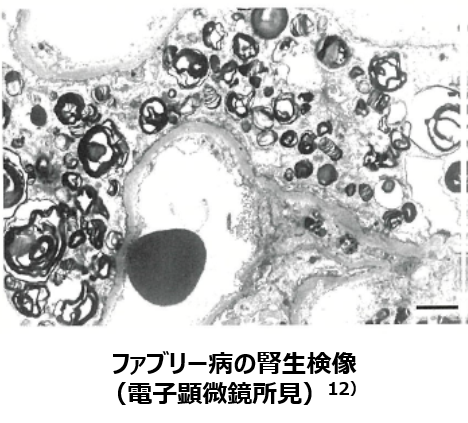

・電子顕微鏡所見では、糸球体たこ足細胞、内皮細胞内などに、「ミエリン状」、あるいは「ゼブラ小体」と表現される沈着物を多数認めます9)。

12)衞藤義勝 総監修 ファブリー病 基礎から臨床までの最近の知見 P.128-132